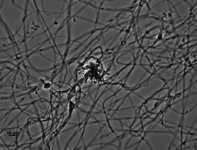

| Species Name: | Nannizziopsis hominis |

| Taxonomy: | FUNGI Ascomycota, Eurotiomycetes, Onygenales, Nannizziopsidaceae |

| Substrate: | abscess right leg, male, HIV positive, same patient as UAMH 7859 |

| Characters: | HUMAN/ ANIMAL PATHOGEN disseminated infection in human - // MOLECULAR SYSTEMATICS phylogeny of Nannizziopsis and reptile pathogens belonging to the CANV complex - Sigler L, Hambleton S, Pare JA, J Clin Microbiol 51:3338-3357, 2013 (Click for publications citing UAMH 7932) |